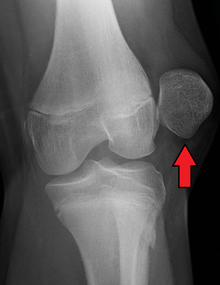

| Radiograph of a patient with patellar dislocation. Normally the patella projects over the distal femur. | |

Patellar dislocation is an injury of the knee, typically caused by a direct blow or a sudden twist of the leg.[1] It occurs when the patella (kneecap) slips out of its normal position in the patellofemoral groove, and generally causes intense pain with swelling of the knee.[1] Open or arthroscopic surgery may be used to repair damage, but are typically avoided since rates of re-injury, knee function, and patients' opinions do not differ much from conservative treatment.[2][3][4]

The patella generally dislocates laterally, and can be accompanied by acute pain and disability. Immediate reduction can be accomplished by hyperextension of the knee, and by providing a medialward pressure to move the patella back into the patellofemoral groove. Hyperextension of the knee on its own could possibly move the patella into place, because this motion locks the knee in place. When the knee is locked the ligaments are twisted and taut, allowing the muscles involved to relax and the patella to slide back into place.[5] If that does not work, a medical professional must manually perform an orthopedic reduction.[1] Swelling and impaired mobility follow patellar dislocation,[6] and a rehabilitation program of six to sixteen weeks is recommended whether or not the patient undergoes surgery.[3]